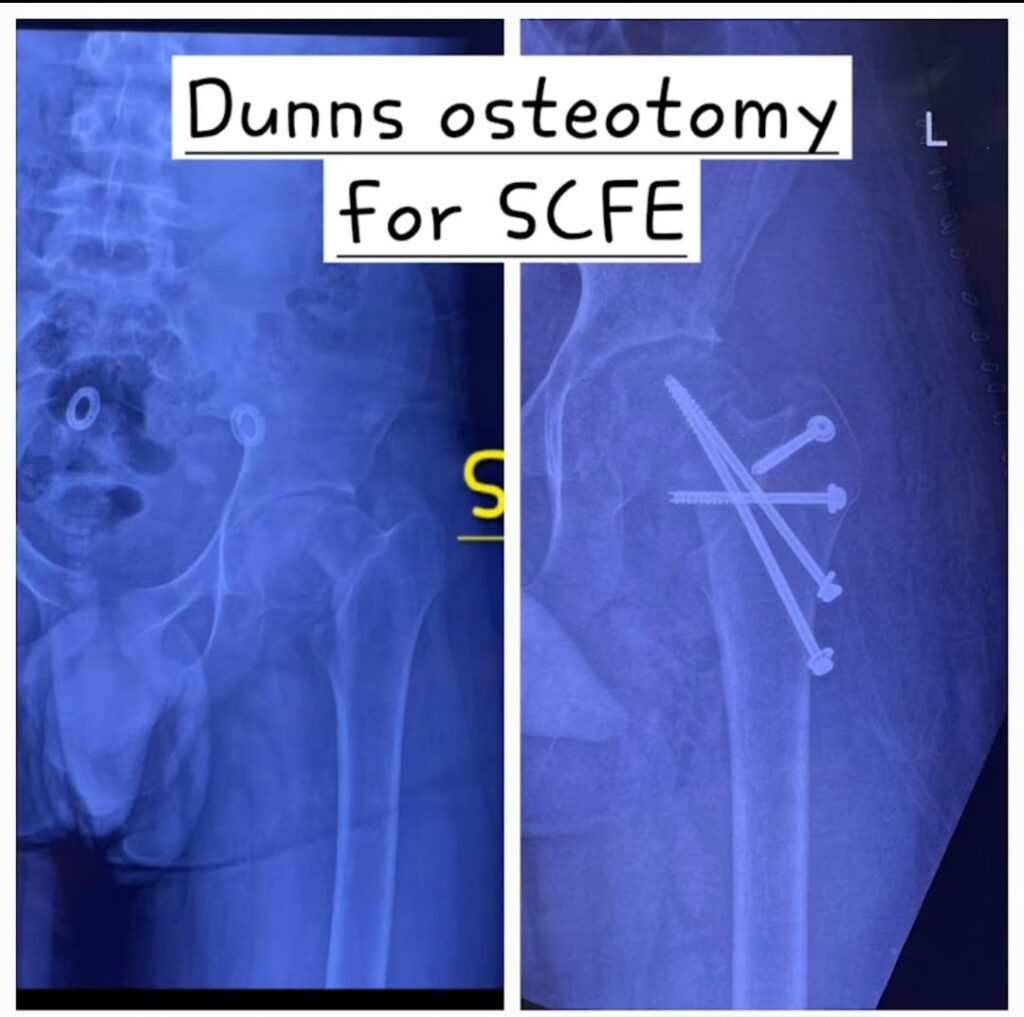

Modified Dunns Osteotomy for Slipped Capital femoral epiphysis